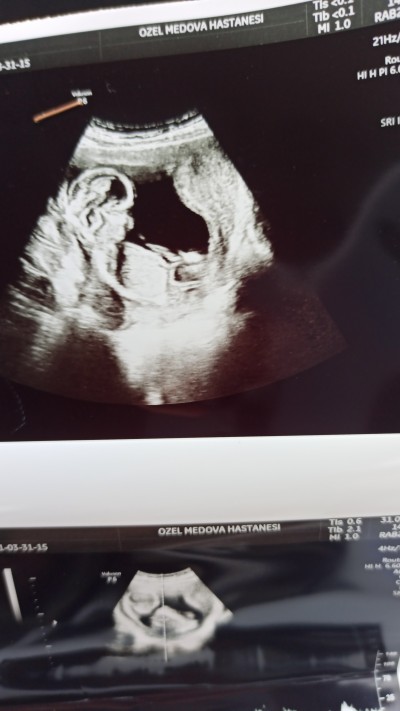

Askolar 15 haftalık olduk cinsiyet tahmini alabilir miyim göstermiyor kendini

image

Direk erkek doğdu içime:)